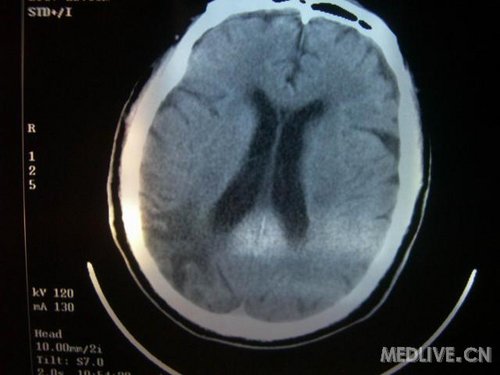

病人男性 73岁 市民 以“幻听、幻视两天,言语含糊、精神错乱一天”入院。

两天前无诱因出现幻听、幻视,描素眼前有彩色的圆圈,听见有人说话(但说什么不详),一天前出现胡言乱语,言语含糊,精神错乱,问话不答,行走略有不稳,来我院就诊,门诊头CT检查:(下面有片)入院后查体不合作,表情淡漠,问话不答,大致检查了一下,颅神经未见明显异常,颈软,右手活动似忽略差。其他检查不配合。脑电图:广泛轻-中度异常。

既往史:半年前曾患“右侧脑梗塞”但无明显后遗症,生活能自理,无高血压、糖尿病、心脏病史。

先传半年前的片子:

此次入院时的片子: